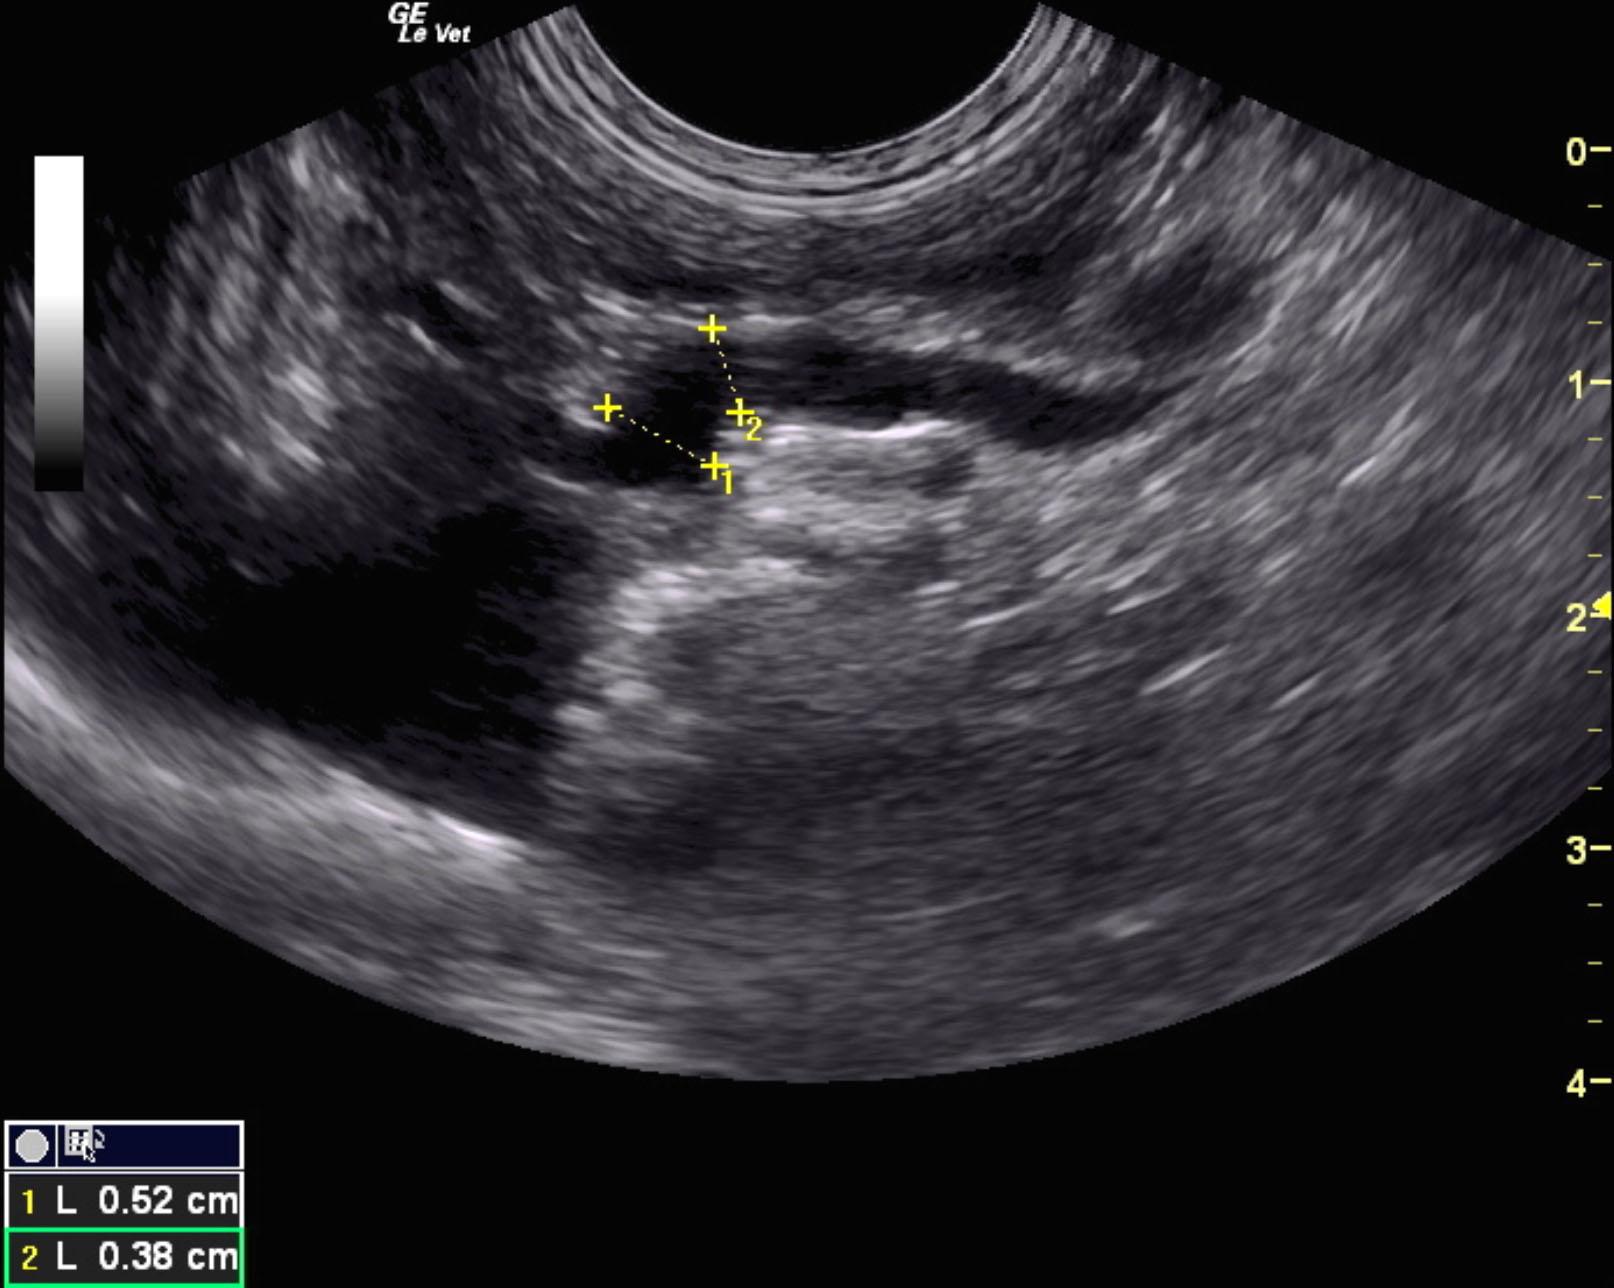

Extrahepatic portosystemic shunt was noted in this patient and measured 0.45 cm in width. The portal vein prior to the shunt measured 0.39 cm and post shunt measured 0.28 cm. This is most consistent with splenocaval shunt. The vena cava prior to the shunt entry measured 0.6 cm and the aorta measured 0.64 cm. The extrahepatic shunt passed dorsally and measured from 0.6 to 1.0 cm in width and entered into the vena cava dorsal ventrally prior to the diaphragm. The vena cava measured 1.0 cm at that point. The liver was subnormal in size and mildly coarse in architecture. The gallbladder was unremarkable.